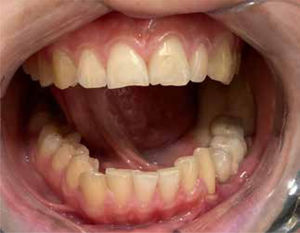

Caso clínicoPaciente 12 años, género femenino, con diagnóstico de sarcoma miofibroblástico mandibular izquierdo. Se realiza resección de tumor con reconstrucción inmediata con colgajo microvascular de fíbula, utilizando la tecnología de planificación virtual.

A los 4 años post reconstrucción, a la paciente se le instalaron los implantes oseointegrados, que permitieron posteriormente realizar la rehabilitación dentaria. Actualmente la paciente está libre de patología, rehabilitada desde el punto de vista funcional y estético y con una oclusión dentaria estable.